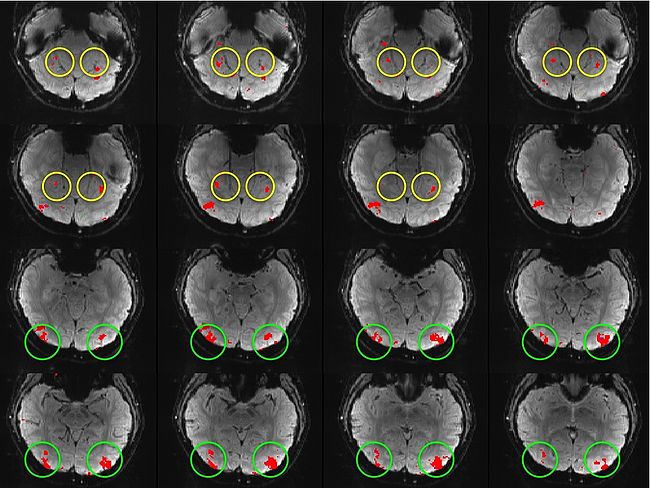

Hierarchical Model for Exploratory fMRI Analysis without Spatial Normalization

Building on the work on the clustering model for the domain specificity, we develop a hierarchical exploratory method for simultaneous parcellation of multisub ect fMRI data into functionally coherent areas. The method is based on a solely functional representation of the fMRI data and a hierarchical probabilistic model that accounts for both inter-subject and intra-subject forms of variability in fMRI response. We employ a Variational Bayes approximation to fit the model to the data. The resulting algorithm finds a functional parcellation of the individual brains along with a set of population-level clusters, establishing correspondence between these two levels. The model eliminates the need for spatial normalization while still enabling us to fuse data from several subjects. We demonstrate the application of our method on the same visual fMRI study as before. Fig. 10 shows the scene-selective parcel in 2 different subjects. Parcel-level spatial correspondence is evident in the figure between the subjects.

| Fig 10. The map of the scene selective parcels in two different subjects. The rough location of the scene-selective areas PPA and TOS, identified by the expert, are shown on the maps by yellow and green circles, respectively. | |